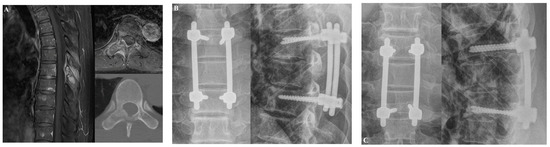

3.1.1. Case 1